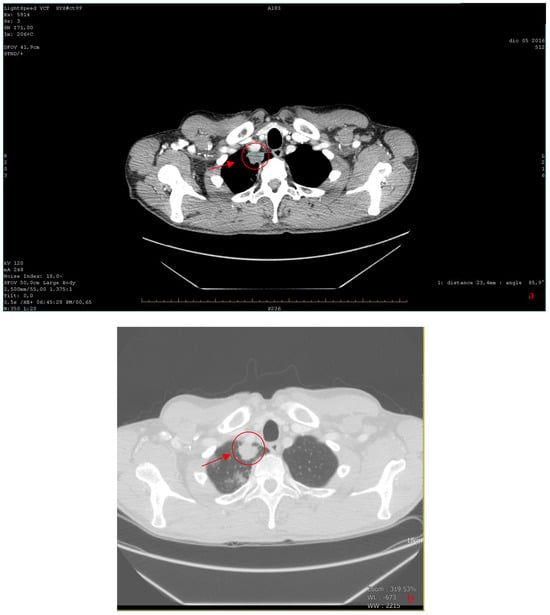

| 2016 | Patient presentation Diagnosis Abdominal ultrasound Total body CT scan  | Worsening non-productive night cough, no dyspnea. Metastatic lung cancer. Presence of malignant lymph nodes near the hepatic hilum. Solid nodular- like expansive process in the right upper lobe of the lung and multiple lymphadenopathies in the mediastinum and abdomen.  |